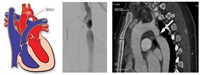

Коарктация - это врожденное сужение самой большой артерии человеческого тела - аорты, которая несет богатую кислородом кровь ко всем органам тела. Это сужение влияет на приток крови к верхним и нижним частям тела и может вызвать высокое кровяное давление или повреждение сердца.

Коарктация препятствует / ограничивает кровоток от сердца к нижней части тела. Артериальное давление становится намного выше нормы в левой камере сердца из-за препятствия, которое сердце должно преодолеть, чтобы продвинуть кровь в аорту. Это может вызвать утолщение (гипертрофию) и повреждение перегруженной сердечной мышцы.

Предварительный диагноз был быстро подтвержден однократной эхокардиографией, проведенной специализированным врачом по ультразвуковому исследованию Аллой Слобозяну.

Обструкцию коарктации можно устранить открытым хирургическим вмешательством или минимально инвазивными эндоваскулярными методами.

Михаил Ташник, интервенционный кардиолог: «Операция проходила в нашей лаборатории ангиографии катетеризации сердца, длилась полтора часа под общей анестезией для удобства пациента и врачей. Через небольшое отверстие на уровне артерии ноги была введена специальная трубка до уровня сужения, где в месте коарктации был имплантирован стент. Стент представляет собой водонепроницаемую медицинскую сетку, которая не только снижает степень сужения, но и сводит к минимуму любой риск возникновения разрыва аорты. Результаты и успешность случая пациентки стали возможны благодаря совместной работе врачей Medpark и коллег из Турции».